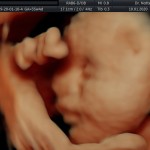

Los objetivos más importantes de esta ecografía son la evaluación de:

- Vitalidad y el bienestar fetal (Doopler).

- Crecimiento fetal.

- La anatomía fetal: Diagnostico de Malformaciones Estructurales de aparición tardía (displasias esqueléticas, alteraciones cardíacas pequeñas, alteraciones de la vía urinaria y obstrucciones intestinales).

- El escenario Gravídico: Placenta, Liquido y Anexos.